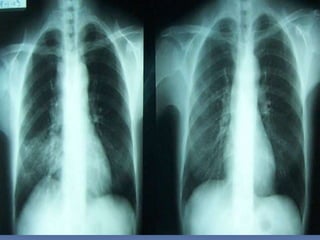

CRITERIOS DE EVALUACION RX.

TX.

 Pulmones desde ápex

hasta senos costo

diafragmáticos

   Pulmones y corazón sin

rotación.

   10 pares de costillas.

   Sombra área de la

tráquea centrada sobre

la columna.

   Balance en los

contrastes de la imagen

(exposición adecuada).

INTERPRETACION

 Revisar estructuras

óseas.

   Partes blandas.

   Espacios intercostales.

   Parénquima pulmonar

   Nivel de los senos

costodiafragmaticos.

   Neumatización.

   Trama alveolo-pulmonar

   Silueta cardiaca

   Cayado aórtico.

CRITERIOS DE EVALUACIONRX. TX.  Pulmones desde ápex hasta senos costo diafragmáticos  Pulmones y corazón sin rotación.  10 pares de costillas.  Sombra área de la tráquea centrada sobre la columna.  Balance en los contrastes de la imagen (exposición adecuada).

INTERPRETACION  Revisar estructuras óseas.  Partes blandas.  Espacios intercostales.  Parénquima pulmonar  Nivel de los senos costodiafragmaticos.  Neumatización.  Trama alveolo-pulmonar  Silueta cardiaca  Cayado aórtico.